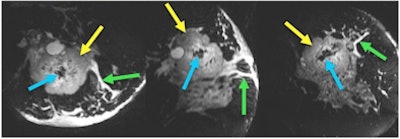

![]() |

| Images utilizing a standard coil and the custom coil, with scan times of four minutes. The vessels and other structures are much more clearly visualized with the 18-channel coil than the standard coil. Image courtesy of Catherine Moran, Stanford University. |